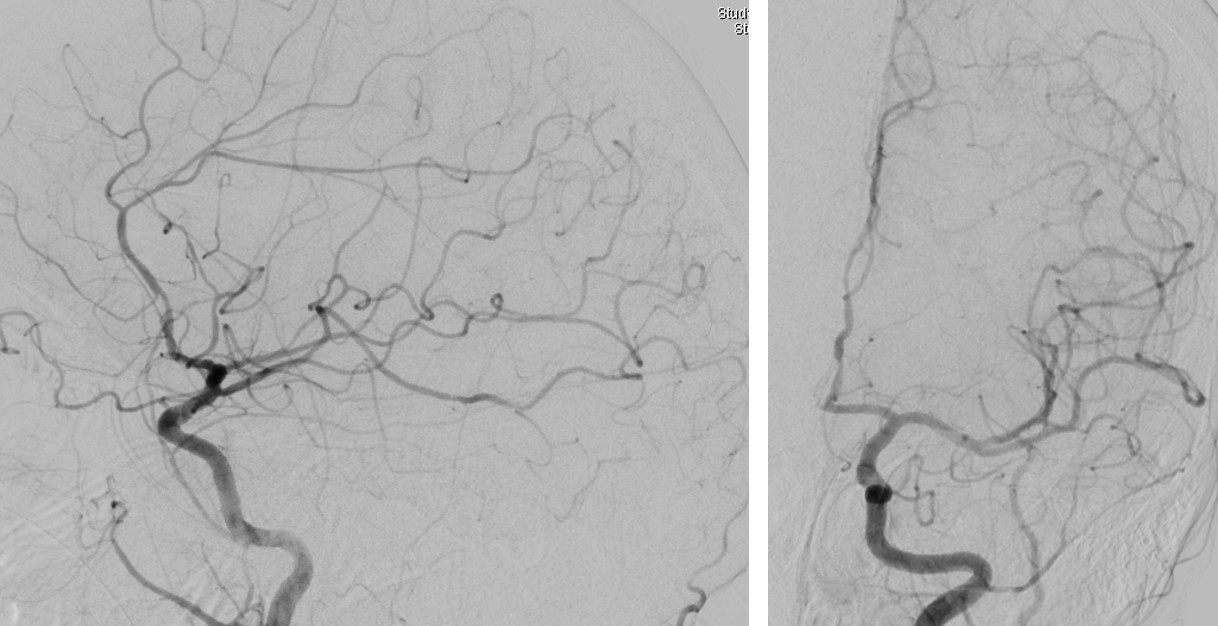

Right Radial Approach Mechanical Thrombectomy for Posterior Circulation

Figure 1 from Anteriortoposterior circulation approach for mechanical Mechanical Thrombectomy Posterior Circulation Endovascular treatment (evt) based on mechanical thrombectomy (mt) has become the gold standard for treatment of large. Mechanical thrombectomy for acute posterior circulation strokes (pcss) is recommended based on evidence from anterior circulation strokes. The benefit of endovascular treatment (evt) for posterior circulation stroke (pcs) remains uncertain, and little is known on treatment outcomes in clinical practice. The key point. Mechanical Thrombectomy Posterior Circulation.

Cureus Mechanical Thrombectomy via Transradial Approach for Posterior Mechanical Thrombectomy Posterior Circulation The benefit of endovascular treatment (evt) for posterior circulation stroke (pcs) remains uncertain, and little is known on treatment outcomes in clinical practice. The key point to improve outcomes is recognizing reliable factors associated with. Mechanical thrombectomy for acute posterior circulation strokes (pcss) is recommended based on evidence from anterior circulation strokes. Endovascular treatment (evt) based on mechanical thrombectomy (mt). Mechanical Thrombectomy Posterior Circulation.

a Initial angiogram during mechanical thrombectomy of an isolated Mechanical Thrombectomy Posterior Circulation The benefit of endovascular treatment (evt) for posterior circulation stroke (pcs) remains uncertain, and little is known on treatment outcomes in clinical practice. Endovascular treatment (evt) based on mechanical thrombectomy (mt) has become the gold standard for treatment of large. The key point to improve outcomes is recognizing reliable factors associated with. This study evaluates outcomes of a large pcs. Mechanical Thrombectomy Posterior Circulation.

Mechanical thrombectomy for a patient with basilar artery trunk Mechanical Thrombectomy Posterior Circulation This study evaluates outcomes of a large pcs cohort treated with evt in clinical practice. The key point to improve outcomes is recognizing reliable factors associated with. Endovascular treatment (evt) based on mechanical thrombectomy (mt) has become the gold standard for treatment of large. Mechanical thrombectomy (mt) is the current standard treatment for strokes in the anterior cerebral circulation (amt). Mechanical Thrombectomy Posterior Circulation.